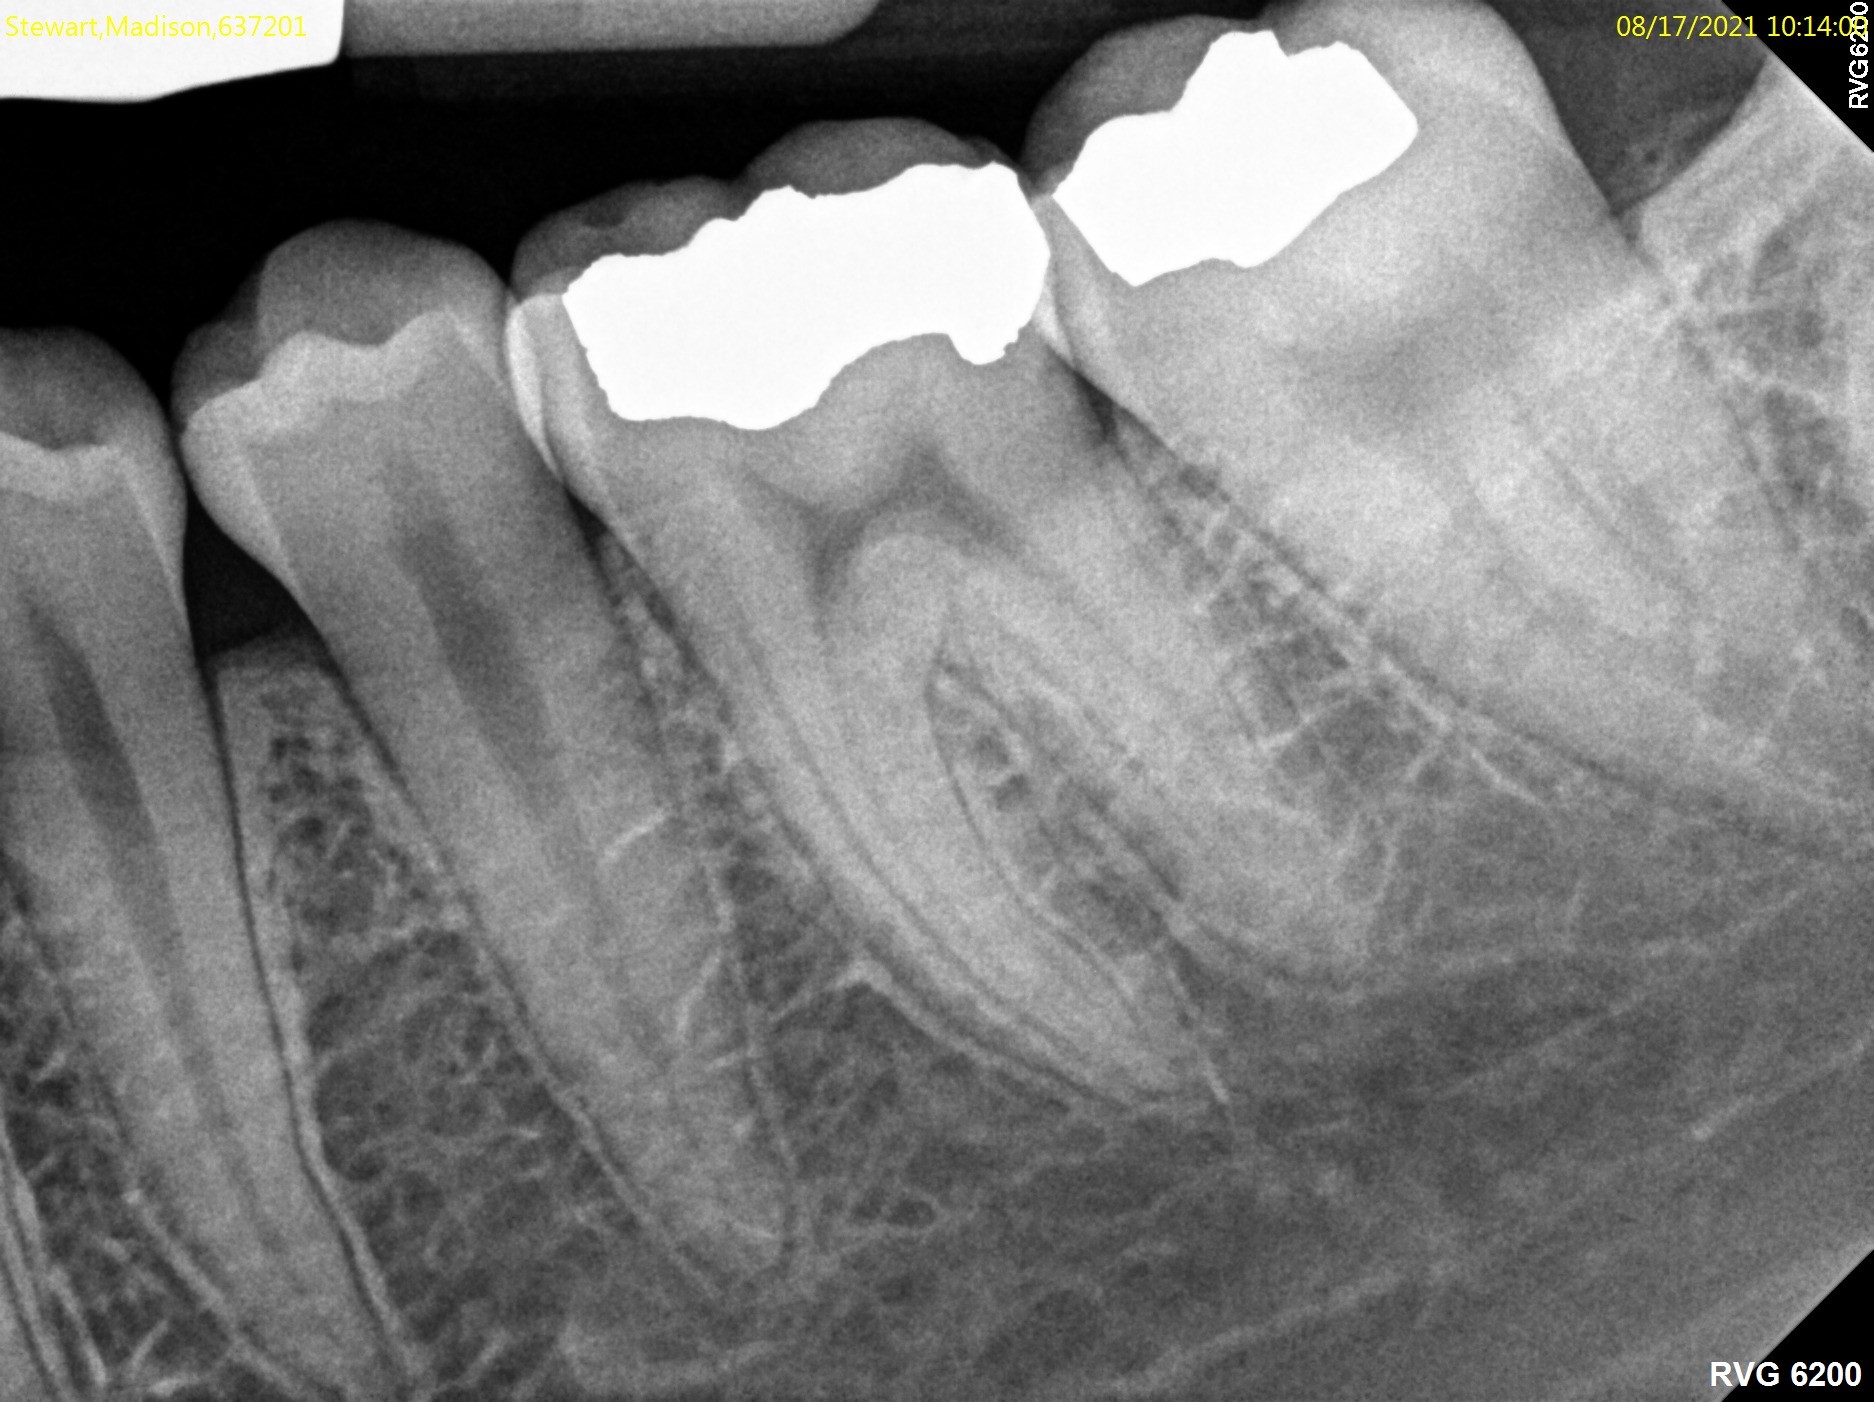

If for any reason the pulp is exposed to the outside, the tissue becomes contaminated and eventually infected. The exposure of pulp happens in many circumstances, such as when you have a large cavity or a fractured tooth. Your dentist can explain the exact reason for damage to this tissue. In these cases, the treatment is usually root canal treatment.

Root canal treatment is the process of going inside the pulp space and removing the inflamed or infected tissue. The space is then disinfected and sealed with special materials. Nowadays, root canal treatments are performed with advanced techniques and materials, making them far more comfortable and less time consuming. After root canal treatment is complete, your restorative dentist will usually place a crown on your tooth to safeguard against fracture.